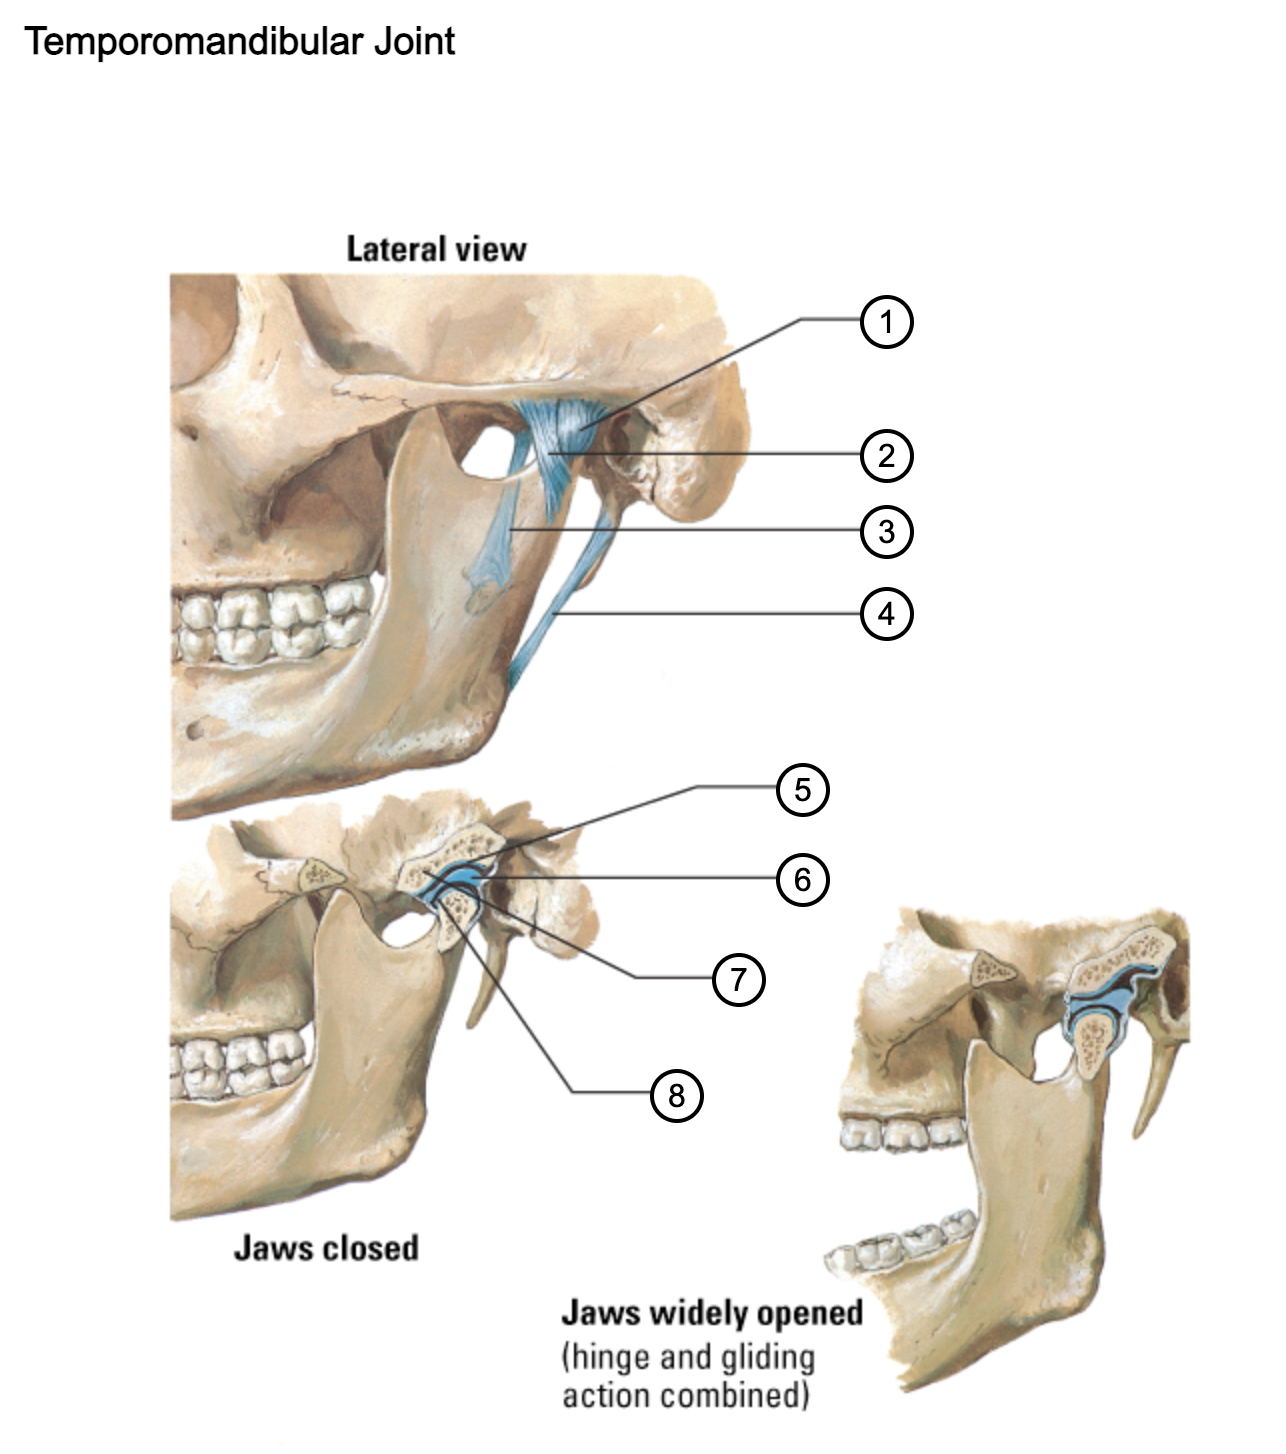

1

capsule of temporomandibular joint

2

lateral temporomandibular ligament

3

sphenomandibular ligament

4

stylomandibular ligament

5

mandibular fossa

6

articular disc

7

articular tubercle

8

capsule of temporomandibular joint